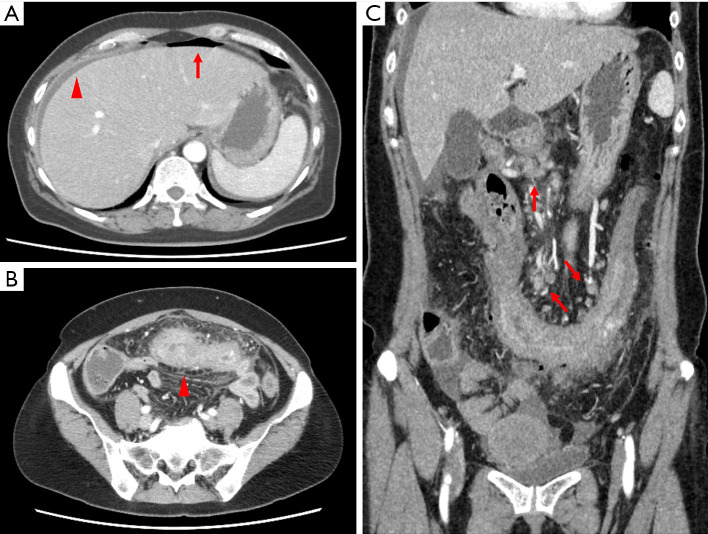

Case description: We describe the case of a 59-year-old woman who underwent right hemicolectomy for a transverse colon perforation and was diagnosed with primary colorectal adenocarcinoma with choriocarcinoma differentiation. Adjuvant chemotherapy with folinic acid, fluorouracil, and oxaliplatin (FOLFOX) and bevacizumab was administered for colorectal adenocarcinoma, but disease progression was observed. The patient had a BRAF V600E mutation, tested negative for human chorionic gonadotropin (hCG), and was switched to a combination of encorafenib, cetuximab, and binimetinib. The treatment response was monitored through regular imaging studies and tumor marker measurements. The patient has been alive for 34 months with no metastases or recurrence, and with continued reduction in the size of the lymph nodes and peritoneal lesions.